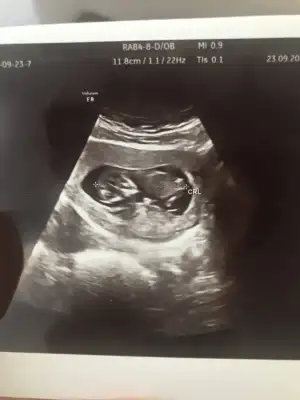

yarın benimde kontrolüm var geçen hafta rahatsızlandıgımda görmeme rağmen bende çok özledim merak ediyorum yaa hayırlısıyla sağlıkla ilerlesin inşaallah hamileliklerimiz